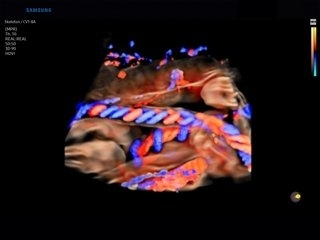

- Crystal Vue и Crystal Vue Flow — объемные изображения мягких тканей и костей с высокой прозрачностью;

- Crystal Vue и Crystal Vue Flow — программа реконструкции прозрачного 3D УЗИ, которое получается при одновременном усилении внутренних и наружных структур. Применяется для визуальной оценки состояния плода и матки, помогает лучше идентифицировать мягкие ткани и кости;

- MV-Flow™ — визуализация микроциркуляции в тканях и органах;

- MV-Flow™ — предлагает новую альтернативу энергетическому доплеру для визуализации медленного потока в микрососудистых структурах. Высокая частота кадров и расширенная фильтрация позволяют MV-Flow™ обеспечивать детальное изображение кровотока по отношению к окружающим тканям или патологическим структурам с улучшенным пространственным разрешением;

- LumiFlow™ — это стереоскопическая визуализация кровотока, которая помогает интуитивно понять структуру кровотока и мелких сосудов;